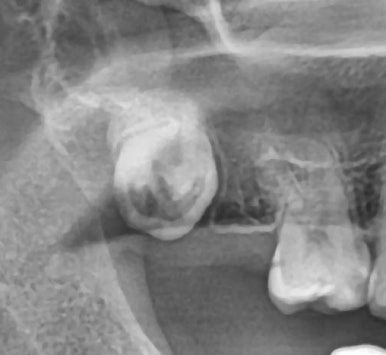

1. 옆으로 누워 난 매복 사랑니

사랑니가 옆 어금니 뿌리를 눌러

충치나 치근 흡수를 유발할 수 있습니다.

| 옆으로 누워나 발치가 필요한 사랑니 | 옆으로 누워난 사랑니를 발치하니, 앞 치아의 충치 발견 |

🔍 실제 사례: 옆으로 누운 사랑니로 인해

앞 치아에 깊은 충치가 생겨 신경치료까지 필요했던 경우가 있었습니다.